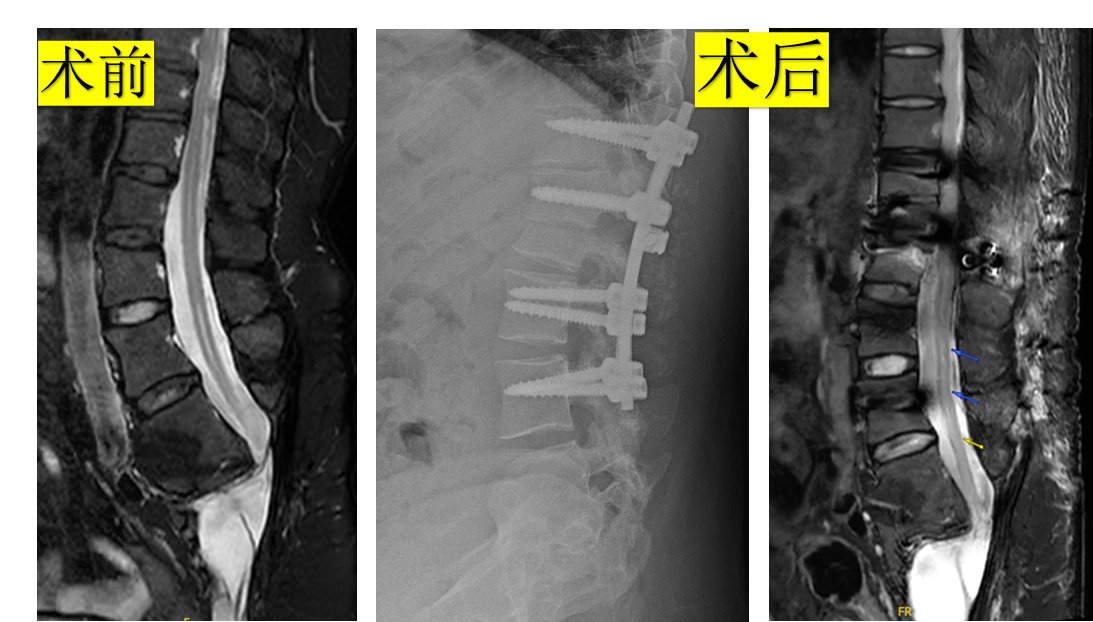

病例2.脊髓拴系、脊髓空洞。行椎体缩短术降低脊髓拴系张力、脊髓空洞好转。